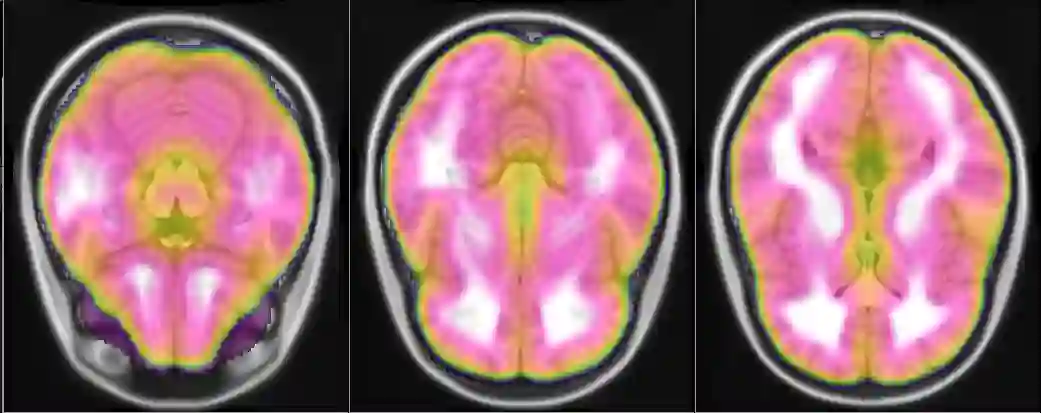

Representational similarity analysis (RSA) is a multivariate technique to investigate cortical representations of objects or constructs. While avoiding ill-posed matrix inversions that plague multivariate approaches in the presence of many outcome variables, it suffers from the confound arising from the non-orthogonality of the design matrix. Here, a partial correlation approach will be explored to adjust for this source of bias by partialling out this confound. A formal analysis will show the dependence of this confound on the temporal correlation model of the sequential observations, motivating a data-driven approach that avoids the problem of misspecification of this model. However, where the autocorrelation locally diverges from the volume average, bias may be difficult to control for exactly (local bias), given the difficulties of estimating the precise form of the confound at each voxel. Application to real data shows the effectiveness of the partial correlation approach, suggesting the impact of local bias to be minor. However, where the control for bias locally fails, possible spurious associations with the similarity matrix of the stimuli may emerge. This limitation may be intrinsic to RSA applied to non-orthogonal designs.